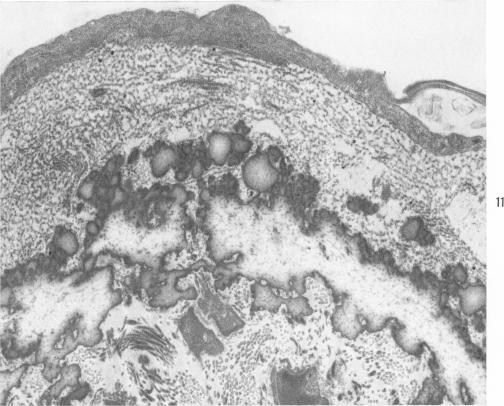

Cardiovascular studies on copper-deficient Swine: x. The fine structure of the defective elastic membranes.

Am J Pathol. 1967 Jul;51(1):117-35.